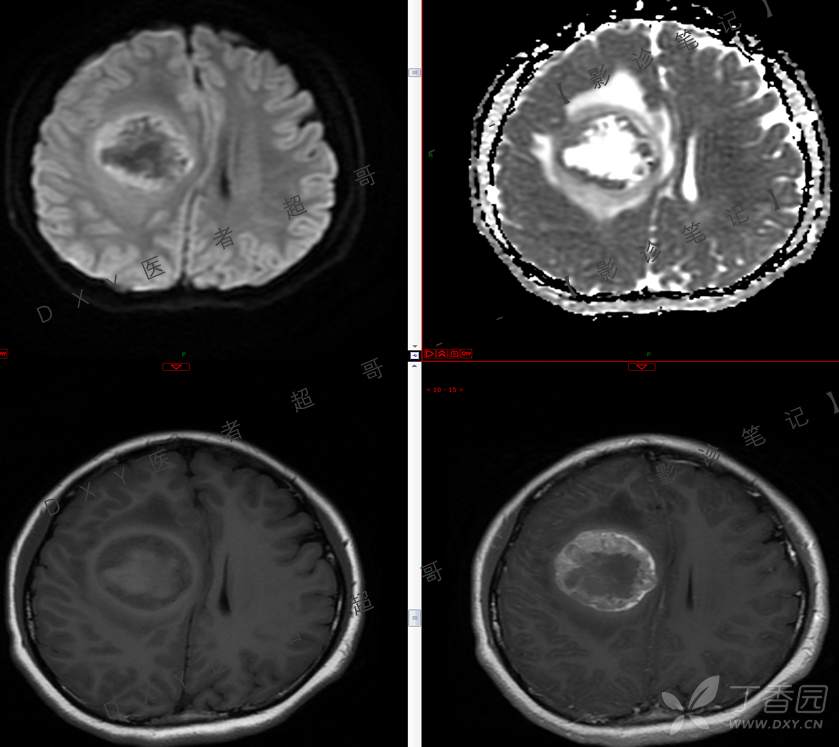

15岁少年,头痛10天,加重伴恶心、呕吐2天,究竟为何?回帖即可查阅病理。

患者年龄:15岁

主 诉:头痛10天,加重伴恶心、呕吐2天。

现病史:患者10天前无明显诱因出现头痛,间断发作,无恶心、呕吐,无肢体抽搐等,于当地医院就诊,体温37.4度,予以对症治疗,具体不详,后症状缓解,2天前患者上述症状较前加重,并感双眼胀痛及视物模糊,伴恶心、呕吐,呕吐数次,为胃内容物,再次于当地医院就诊,行颅脑CT考虑“右侧额顶叶病变”,现为求进一步治疗来我院急诊就诊,以“脑脓肿?”收入我科。患者病来精神差,饮食、睡眠欠佳,体重无明显变化。